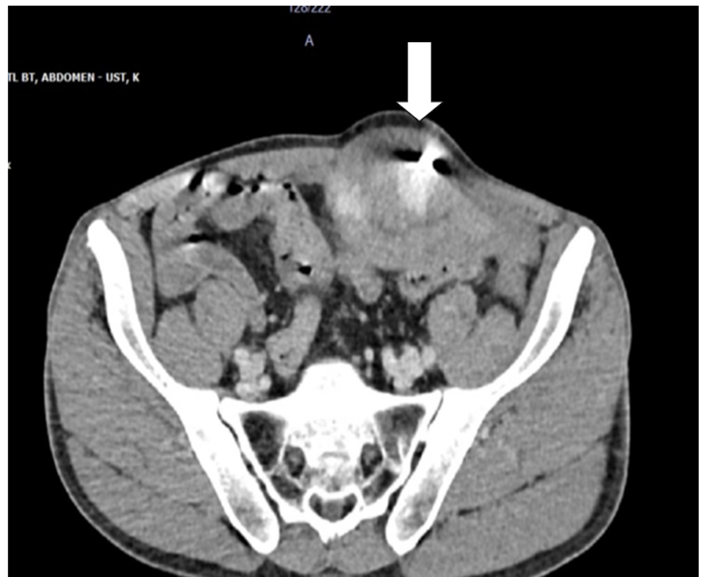

Laboratory tests revealed an elevated white blood cell count of 15.2 × 10⁹/L (reference: 4-10 × 10⁹/L), C-reactive protein of 28 mg/L (<5>(Figure 1).

Figure 1: Abdominal Pelvic Computed Tomography showing foreign body in left rectus sheath